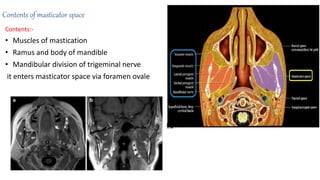

Contents of masticator space

Contents:-

• Muscles of mastication

• Ramus and body of mandible

• Mandibular division of trigeminal nerve

it enters masticator space via foramen ovale